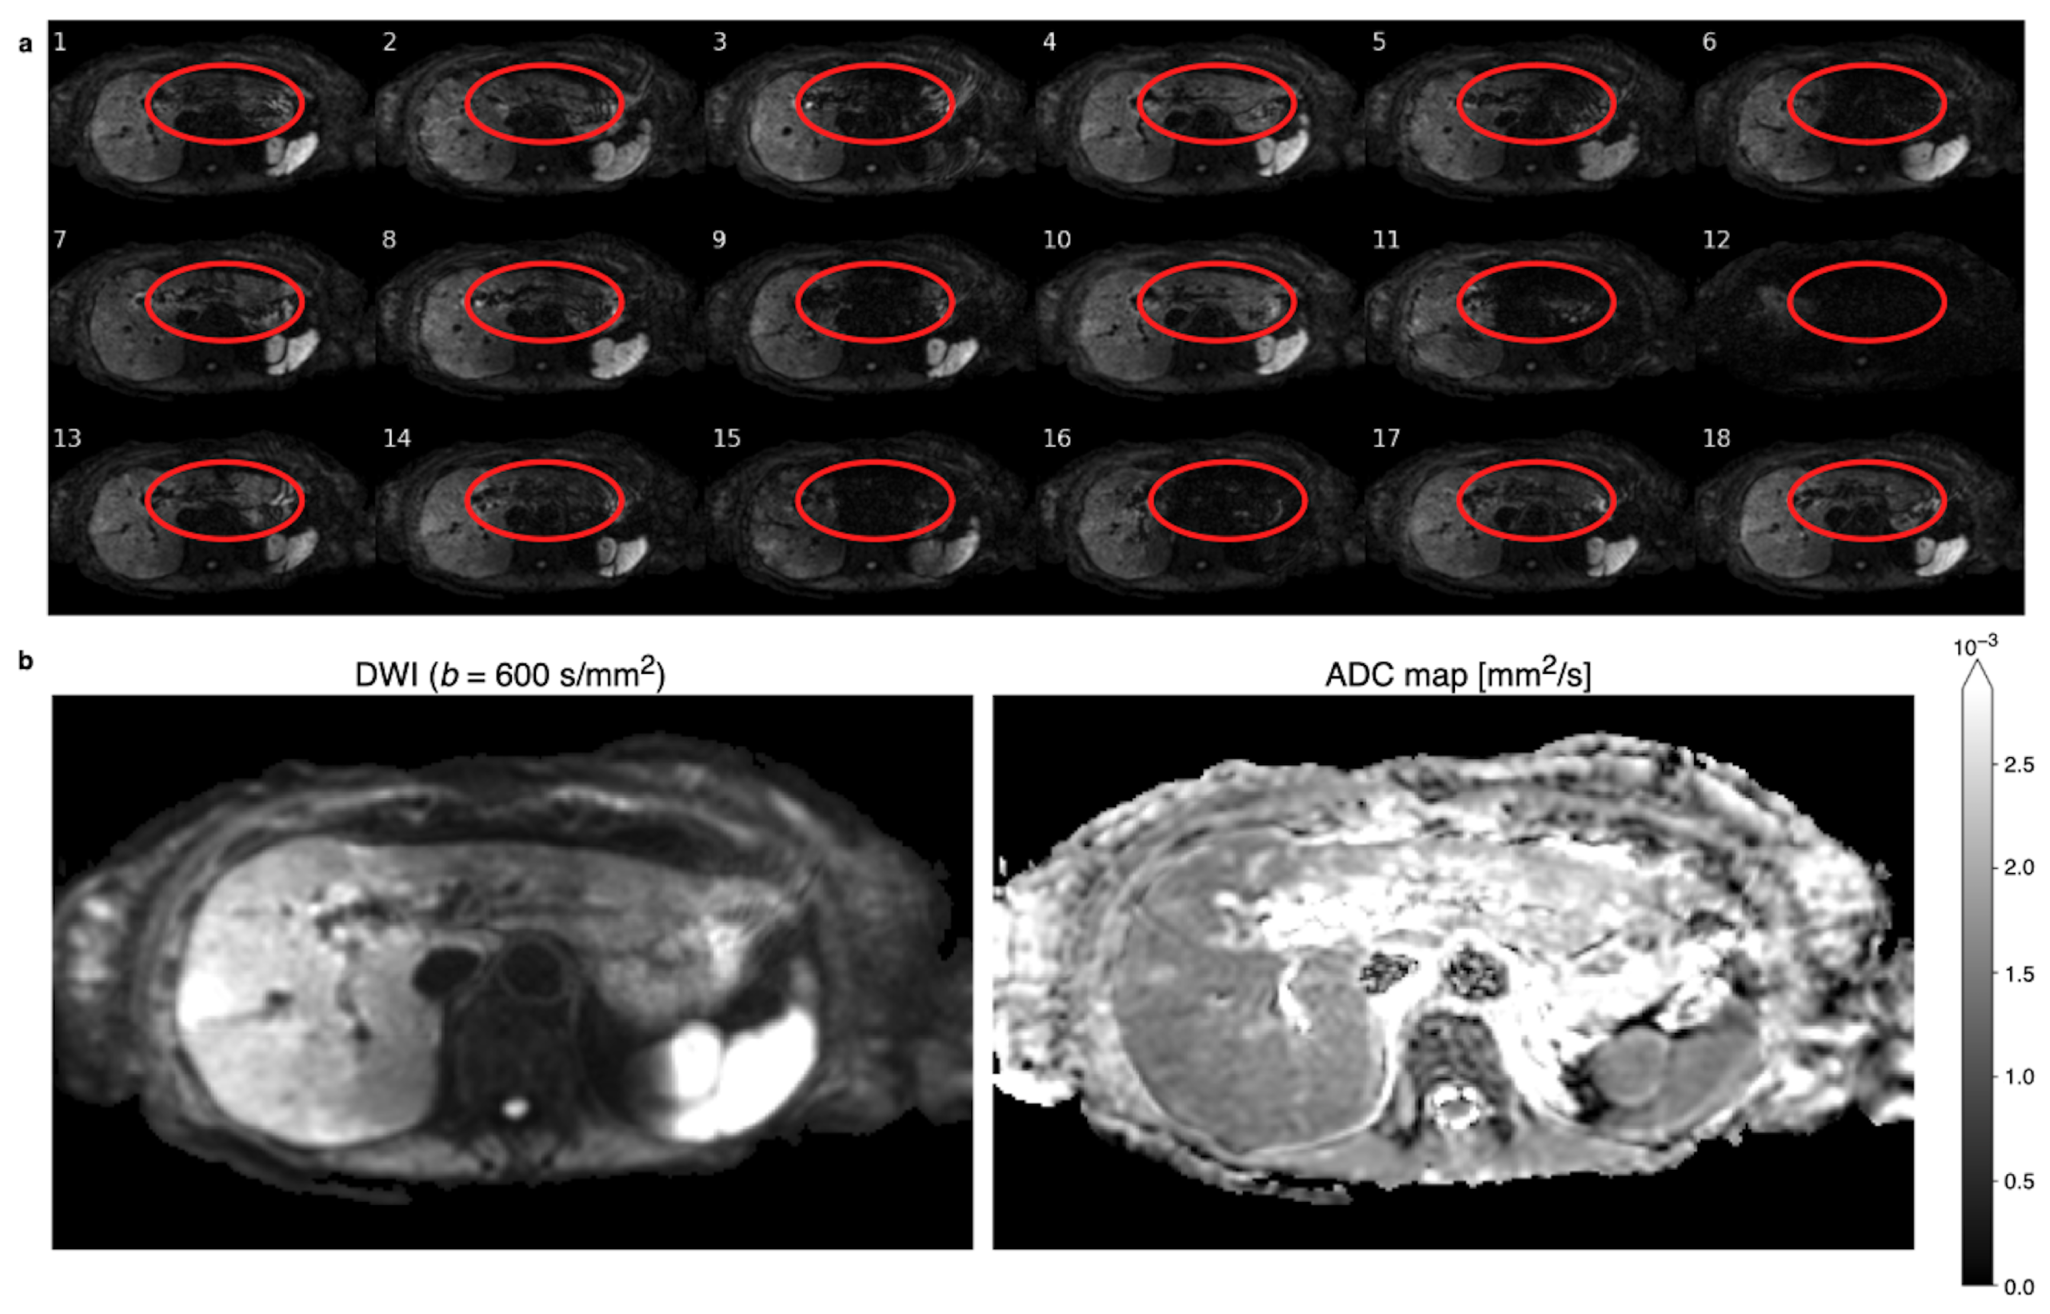

2. Materials and Methods

2.1. Implicit Weighted Averaging

2.2. Spatial Scaling for the Reduction of Motion-Induced Signal Loss

2.2.1. Rejection Process

3.1. Repetition and Voxel Rejection